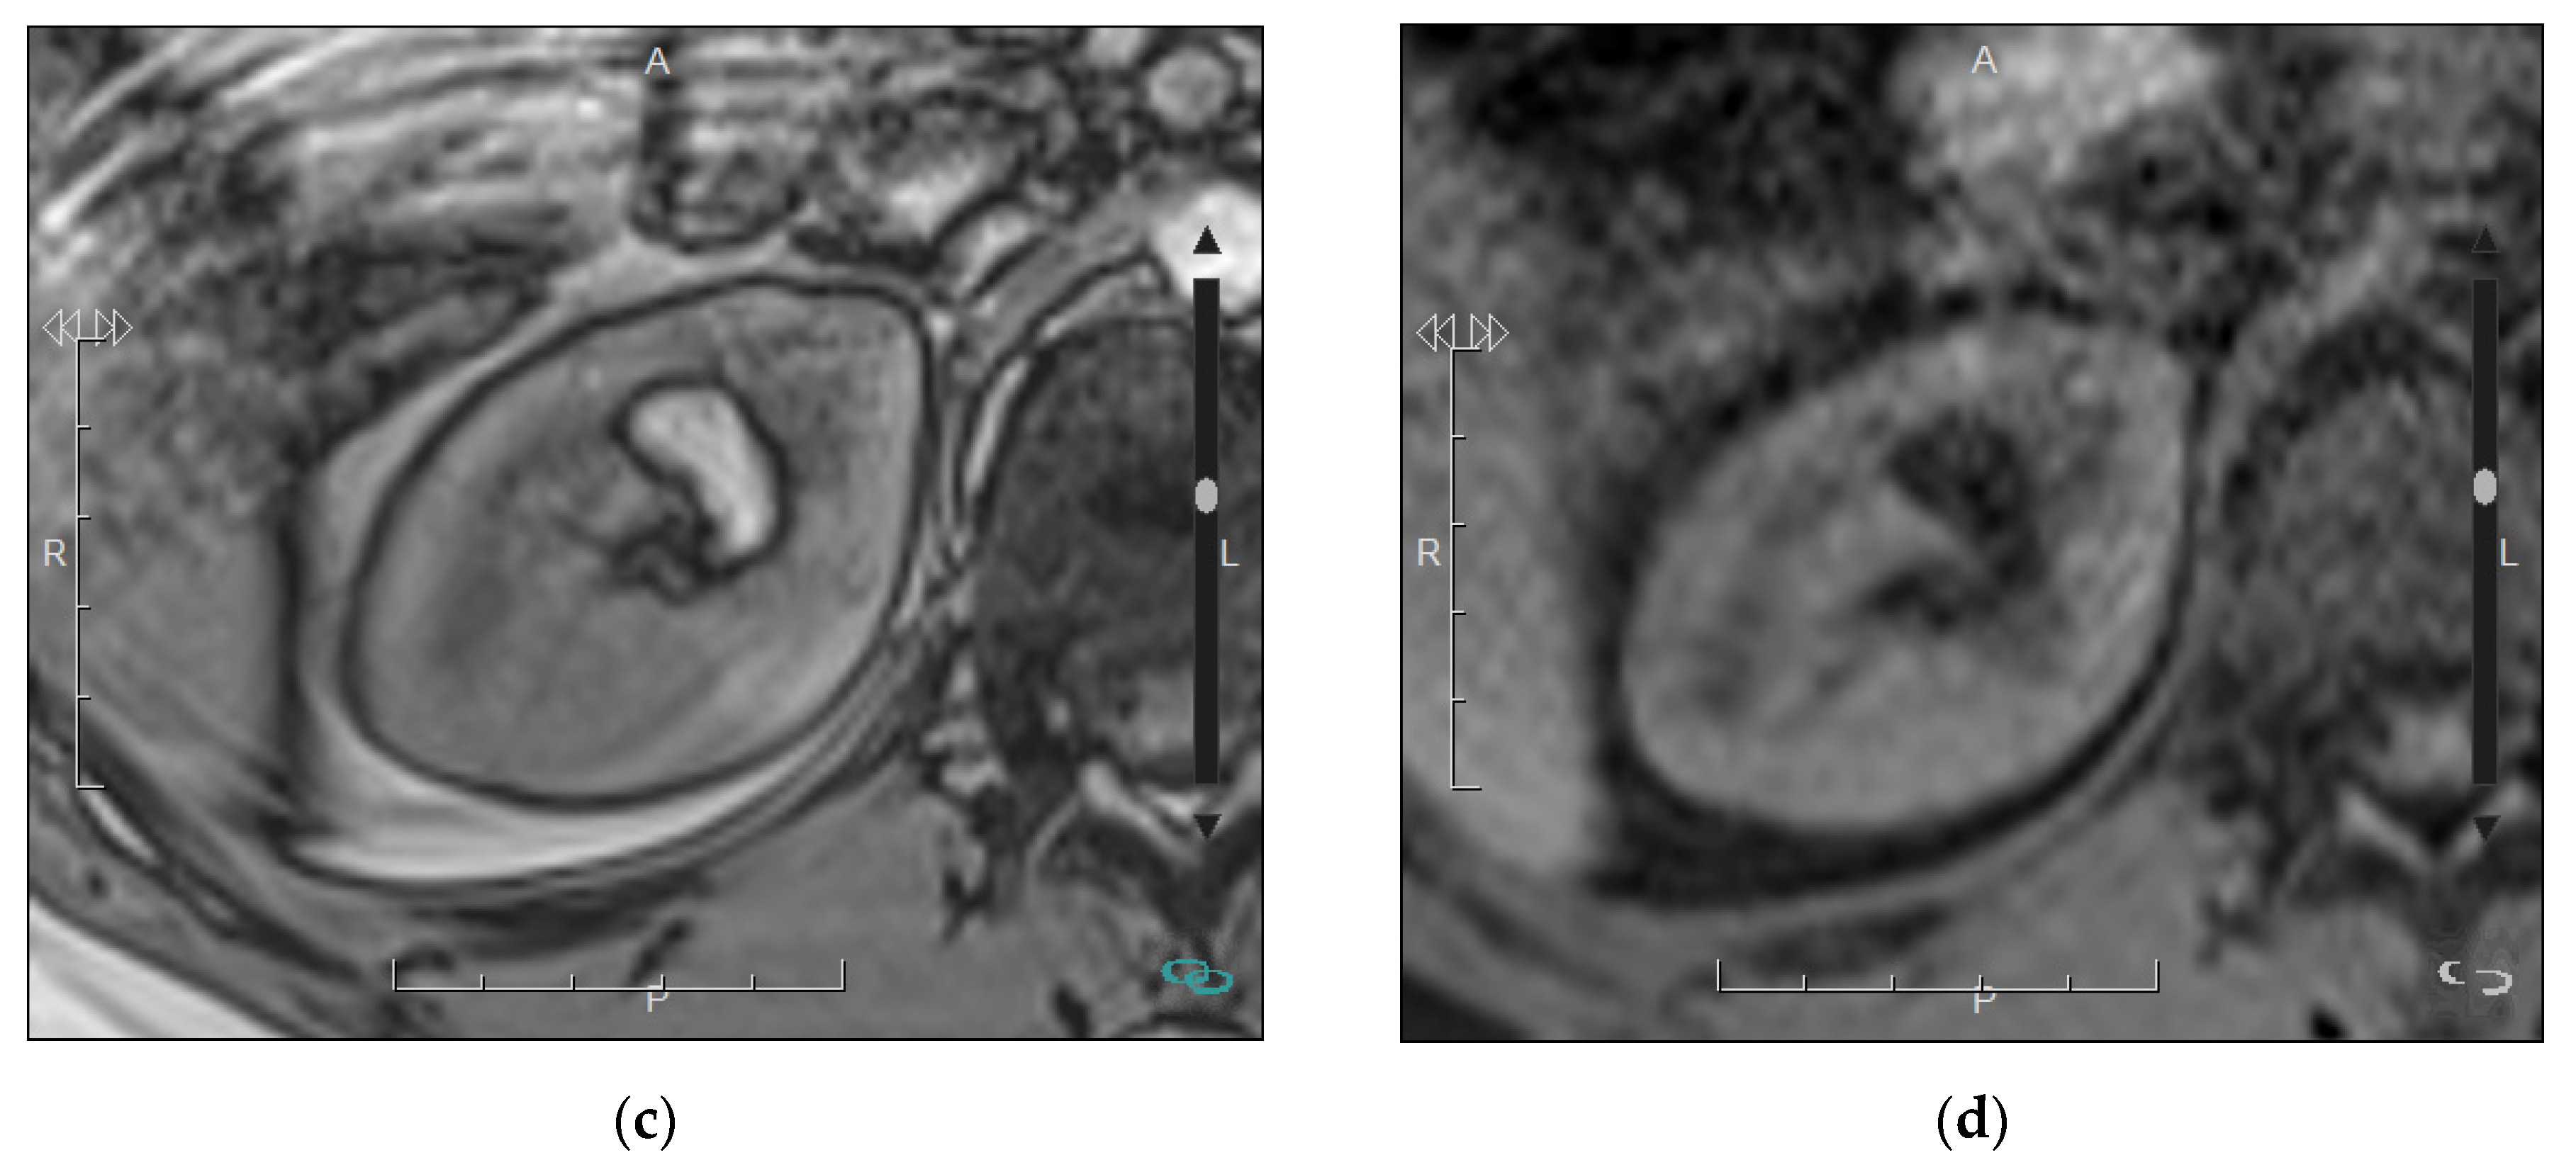

4.1. Nodular Masses

| Renal Lesion | Morphologic Findings | MRI Signal Intensity | Enhancement | Diffusion |

|---|---|---|---|---|

| Typical AML | Macroscopic fat detection | Signal loss on Fat-saturation sequence. | Variable depending on the amount of adipose tissue, smooth muscle and blood vessels | No obvious restriction. Low signal on the ADC map due to the presence of fat. |

| Fat-poor AML | Hyperdense on unenhanced CT (basal CT) | Hypointense signal on T2 | Variable. Usually homogeneous and prolonged | No obvious restriction. |

| Oncocytoma | Central scar (<50% cases) | Variable, but mainly hyper- or iso-intense. | Hyperenhancement on corticomedullary phase. Segmental enhancement inversion 1 | No obvious restriction. |

| Clear cell RCC | Occasional calcifications. Occasional central scar. | May show loss of signal intensity on opposed-phased sequence (due to the presence of microscopic fat) | Hyperenhancement on corticomedullary phase Heterogeneous if haemorrhagic, cystic, or necrotic areas. | Variable restriction depending on the differentiation. |

| Papillary and chromophobe RCC | Occasional calcifications. | Papillary RCC may show hypointensity on T2. | Iso-hyperenhancement on nephrographic phase Homogeneous. Occasionally very scarce enhancement (papillary RCC). | Papillary RCC: Greater restriction than clear cell RCC. |